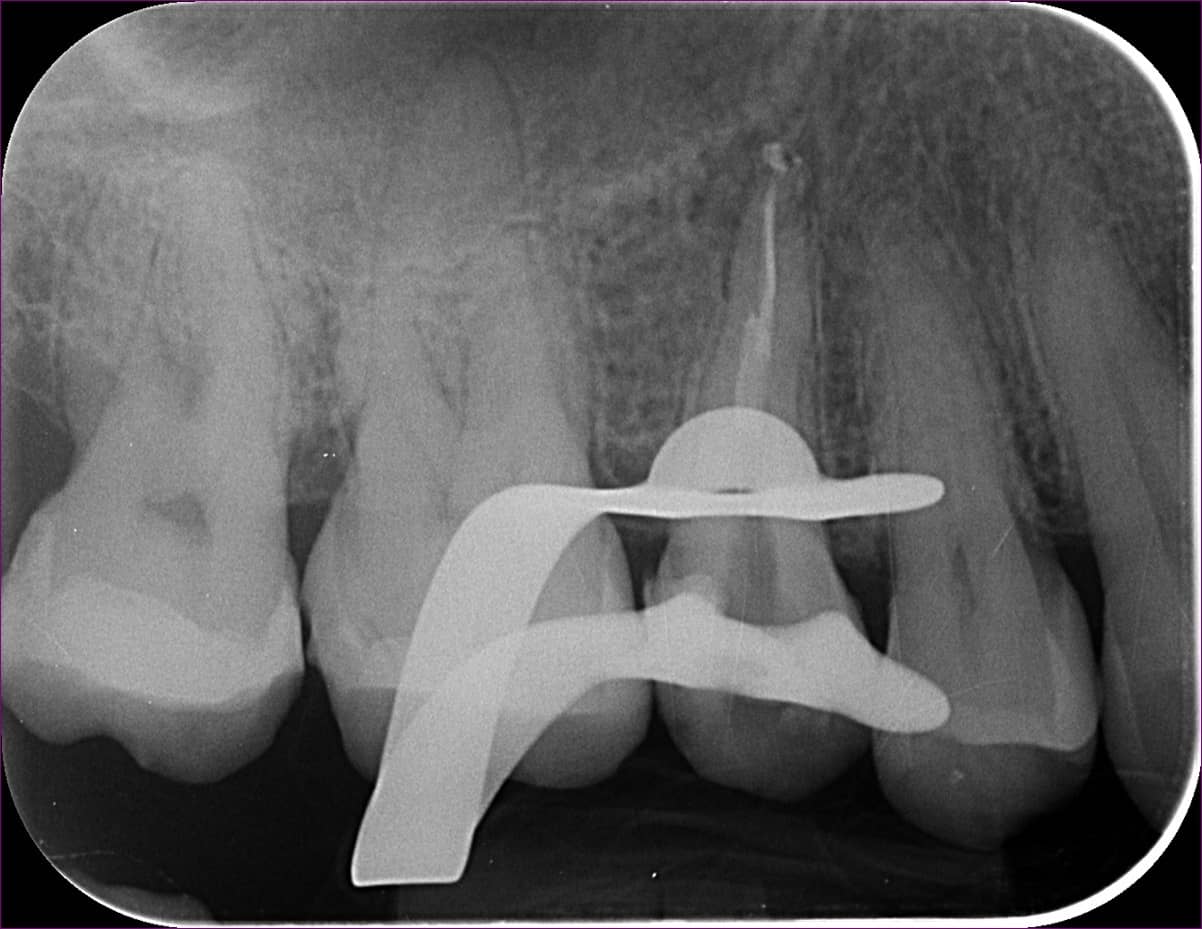

A végleges gyökértömés

Kis korrekció, és egy ismételt fertőtlenítési protokoll után pedig elkészítettük a gyökértömést. A kezelés még egy alkalmat vett igénybe, az ún. üvegszálas csapos megerősítést ekkor helyeztük a fogba. Ez nem kötelező lépés a gyökérkezelések menetében, ám ezúttal volt szükség rá. A csapos megerősítés ugyanis egyfajta belső merevítésül szolgál, védi a maradék foganyagot a későbbi törésektől, illetve viseli a koronát, ami pár hét után készül majd a fogra.

A gyökértömést követően páciensünk szinte teljesen tünetmentes volt. A gyökérkezelések után megszokott, pici érzékenységen kívül fájdalmai, panaszai nem voltak. Végtelenül örült annak, hogy elkerülhette a foghúzást, és megkönnyebbült, mert a mikroszkópos gyökérkezelés egyáltalán nem bizonyult félelmetesnek. Sőt, bevallotta, hogy a fekvő helyzetben végzett kezelések során mindig kellemesen ellazult, már-már elszundikált!